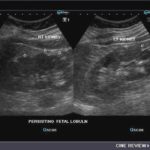

5-Fetal lobulations

في مرحلة تطور الجنين تتكون الكلية عن طريق تلاحم عدة فصوص lobes. وهذه الفصوص قد تستمر إلى مابعد مرحلة البلوغ. تظهر بشكل تموجات في القشرة الخارجية للكلية. من المهم أن لا نخطئ في تشخصيها كندبة scar أو ورم في الكلية.